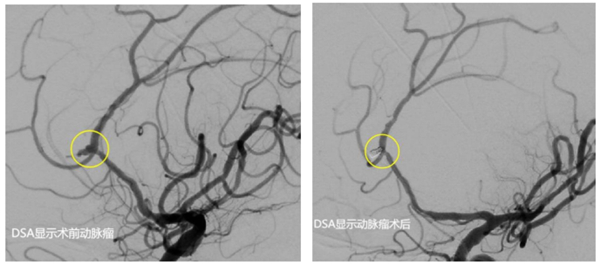

经和家属协商,同意进行手术。该院神经外科介入团队立即启动手术预案。麻醉医师、手术室护士、导管室医护等提前做好术前准备。麻醉成功后,先行脑室钻孔引流,为动脉瘤栓塞争取更多时间。而后,顺利找到了破裂出血的动脉瘤并完美致密填塞,出血情况得到控制。历经4个小时的救治,最终将患者从死亡边缘拉了回来。